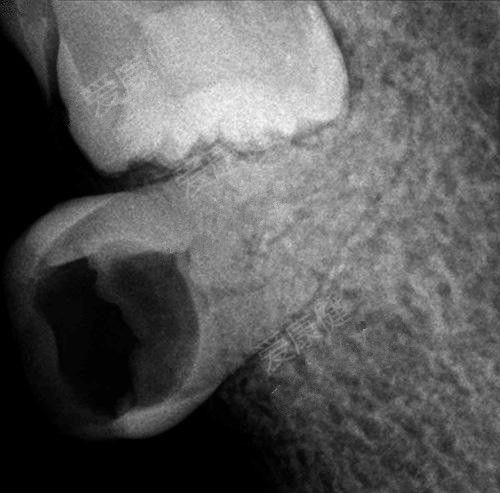

6、拔牙鑲牙

好了,如果你還拖著不去治療,等到大部分殘根被蛀沒了需要拔除,那就需要拔牙再重新鑲牙了。

拔牙的價(jia) 格大概在幾百元左右,難拔的牙齒可能需要用到幾千元。當然不是拔牙後就完事了,後期還需要進行鑲牙。常見的鑲牙方式有三種:活動假牙、固定假牙和種植牙。活動假牙的價(jia) 格在數百到上千元左右,固定假牙的價(jia) 格在千多到八九千不等,在萬(wan) 多到兩(liang) 萬(wan) 多不等。其中種植牙由於(yu) “牙根獨立存在、不磨損鄰牙、使用時間長”等特性,逐漸受到缺牙**們(men) 的喜愛。